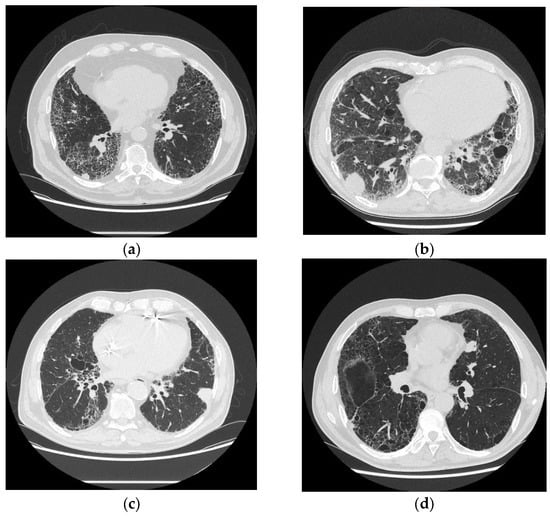

- Galioto, F.; Palmucci, S.; Astut, G.M.; Vancheri, A.; Distefano, G.; Tiralongo, F.; Libra, A.; Cusumano, G.; Basile, A.; Vancheri, C. Complications in Idiopathic Pulmonary Fibrosis: Focus on Their Clinical and Radiological Features. Diagnostics 2020, 10, 450. [Google Scholar] [CrossRef]

- Baratella, E.; Fiorese, I.; Marrocchio, C.; Salton, F.; Cova, M.A. Imaging Review of the Lung Parenchymal Complications in Patients with IPF. Medicina 2019, 55, 613. [Google Scholar] [CrossRef]

- Oh, S.Y.; Kim, M.Y.; Kim, J.-E.; Kim, S.-S.; Park, T.S.; Kim, D.S.; Choi, C.-M. Evolving Early Lung Cancers Detected During Follow-Up of Idiopathic Interstitial Pneumonia: Serial CT Features. Am. J. Roentgenol. 2015, 204, 1190–1196. [Google Scholar] [CrossRef] [PubMed]